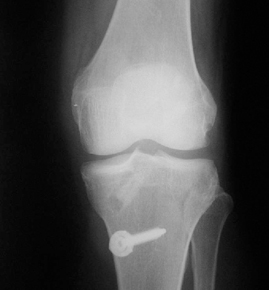

• ACL 손상 방사선 사진3